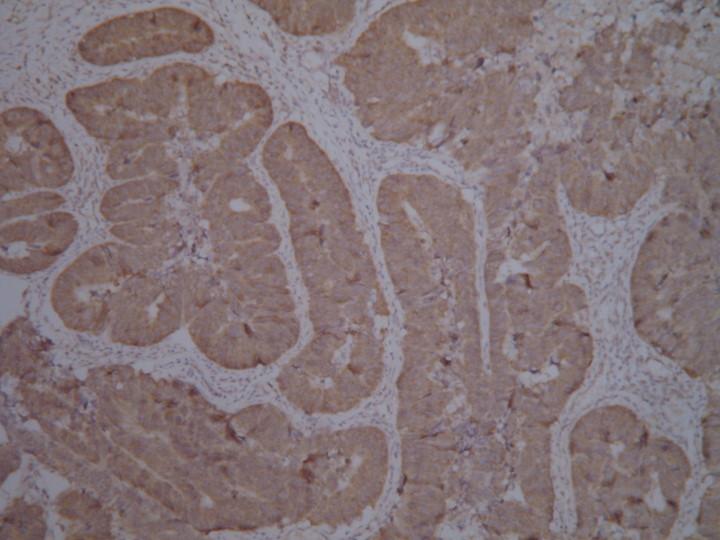

小弟第一次做免疫组化,请各位达人评价一下效果

小弟我第一次做免疫组化 用的SP三步法,DAB染色 但是不知道效果如何,请各位有经验的达人评价一下效果以及可以改进的地方 ![]() [ Last edited by beyo on 2011-9-1 at 10:11 ] |